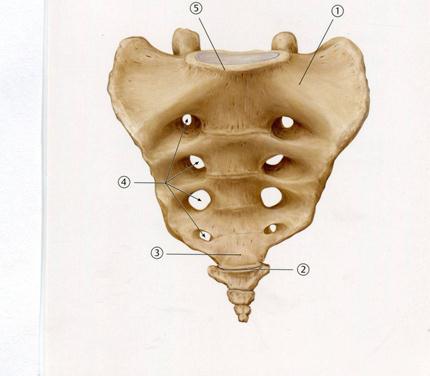

А. Алдыңғы сегізкөз тесіктері

В. Астаулық беті

С. Бүйір бөлімі

+++++D. Негізі

Е. Ұшы

A. Аралық сегізкөз қырқасы

B. Құлақ қалқан буын беті

C. Латеральды сегізкөз қырқасы

+D. Ортаңғы сегізкөз қырқасы

E. Сегізкөз өзегі